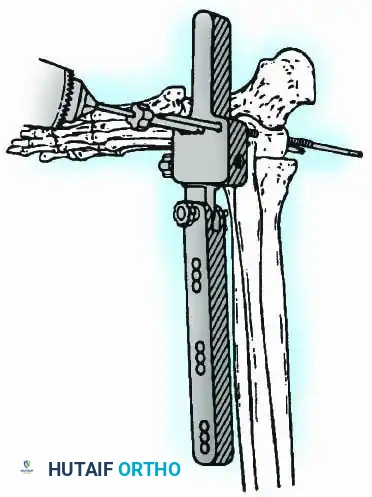

External Fixation

Historically pioneered by Charnley, external compression arthrodesis utilizes pins placed through the distal tibia and the body of the talus. Because Charnley's original uniplanar device lacked rotatory stability, Calandruccio designed a triangular frame to control motion in all three planes while applying massive compression.

Modern iterations, such as the Calandruccio II compression device, offer greater latitude in pin placement to avoid compromised skin. Ring or circular external fixators (Ilizarov, Taylor Spatial Frame) are the gold standard for salvage situations, including active infection, massive bone loss, or failed TAA, as they allow for simultaneous compression, deformity correction, and early weight-bearing.